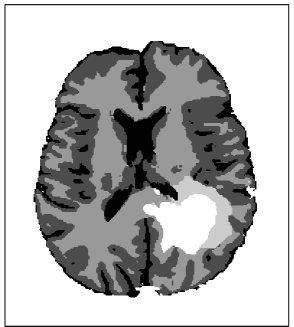

Refer to caption

Figure 2: Segmentation of the brain into contrast enhancing core (white), peritumoral edema, white matter, gray matter, and CSF (black).

In the first data processing step, all MR sequences are registered to the image with highest spatial resolution. This is done using rigid registration with 6 degrees of freedom, utilizing the function FLIRT [31] as part of the toolbox FSL [32, 33]. In the second step, a segmentation of the brain was obtained using the multimodal brain tumor segmentation algorithm published in [34]. The algorithm is an Expectation-Maximization (EM) based segmentation method, which uses a probabilistic normal tissue atlas as spatial tissue prior. For every voxel, it estimates the posterior probability for three normal tissue classes (white matter, gray matter, and CSF111In this work, we refer to all brain tissue that is neither white matter, gray matter, nor tumor as CSF.), as well as the lesion outlines on T1 post gadolinium and T2-FLAIR. The result of the EM segmentation is augmented as described in [35] in order to facilitate a reliable identification of falx cerebri and tentorium cerebelli as anatomical barriers. The segmentation result for the patient in figure 1 is shown in figure 2. In the last step, the reference MR image is registered to the radiotherapy planning CT using rigid registration. The transformation matrix is saved and later applied to register the simulated tumor cell density to the planning CT.